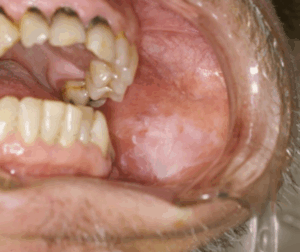

白板症

舌の側面や縁に白い斑点や膜状のできものが現れ、痛みがほとんどない場合は「白板症」の可能性があります。

白板症自体は良性ですが、一部が舌がんへ移行するリスクがあります。

痛みがないからと軽視せず、定期的にセルフチェックを行い、変化が見られる場合には歯科口腔外科や耳鼻咽喉科などの医療機関を受診することが、早期発見・早期治療につながります。